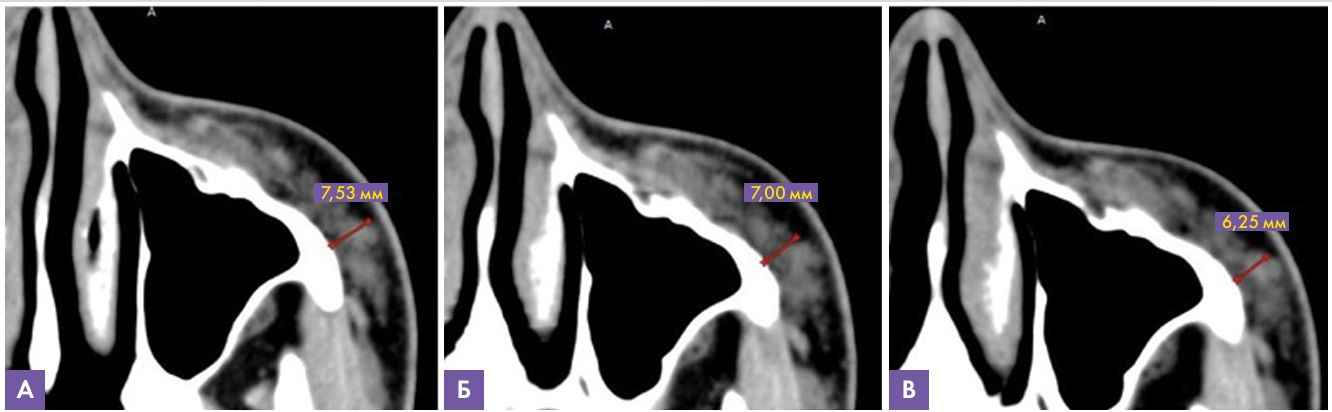

Данные МСКТ (рис.6): на аксиальном срезе скуловой области слева при динамическом исследовании через 12 месяцев после введения имплантата на основе гиалуроновой кислоты отмечается уменьшение толщины слоя от кости до уровня SMAS с 7,9 мм до 6,25 мм (толщина вышеописанного слоя до инъецирования составляла 4,7 мм). Данных за наличие инфильтративных изменений, признаков миграции и инкапсулирования препарата не выявлено.

Рис. 6. МСКТ сканы левой скуловой области, аксиальная проекция

А – через 5 месяцев, толщина имплантата 7.53 мм

В – через 9 месяцев, толщина имплантата 7.00 мм

С – через 12 месяцев, толщина имплантата 6,25 мм